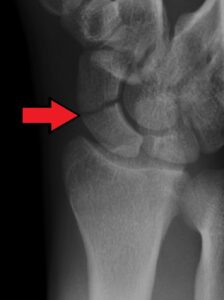

Imaging

• X-ray at least AP and lateral

• Consider MRI as first line for suspected scaphoid fractures following thorough clinical examination (3).

• CT scans are also often used to help further visualise the fracture and are recommended by the BSSH pathway (see (4)).

• Important to note:

• Location of fracture (distal pole, waist, proximal pole)

• Any displacement

• Any articular surface involvement